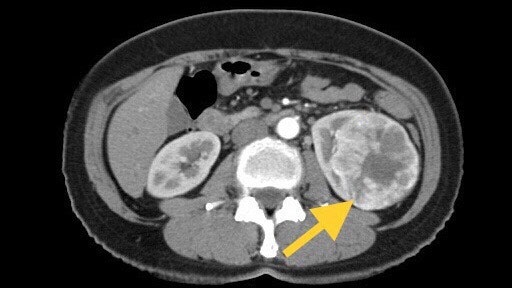

신장질환 진단에 있어 복부초음파는 가장 흔하고 비침습적이며 많은 정보를 얻을 수 있고 복막 내 다양한 장기를 관찰할 수 있다. 최근에는 건강검진 시 복부 초음파 검사를 자주 시행하여 새로운 종양을 조기에 발견하는 경우가 많습니다. 복부초음파에서 신장에 낭종이 발견되면 단순낭종인지 복합낭종인지 고형종양인지 구분할 수 있다고 합니다. 조영제를 사용한 CT 스캔이 권장됩니다.신장 낭종 치료

대부분의 단순 신장 낭종(신장 낭종)은 특별한 치료가 필요하지 않으며 정기적인 추적 검사로 충분합니다. 그러나 신장 낭종(콩팥낭종)이 매우 크고 관련 증상이 있는 경우에는 대증적 치료가 필요합니다. 단순 신장 낭종(신장 낭종)은 신장이 있는 쪽에 구멍을 뚫어 카테터를 삽입하고 내부의 용액을 배출한 후 카테터를 통해 약물을 주입하여 낭종이 융합되도록 함으로써 치료합니다.

드물게 낭성 신장암이 의심되는 경우 신장을 제거하는 수술이 필요할 수 있습니다. 이때 수술은 신낭종(콩팥낭종)의 크기에만 의존하지 않는다고 합니다. 신장 낭종(신장 낭종 또는 신장 낭종)으로 인한 합병증이 있거나 영상 검사에서 악성 가능성이 있는 경우 수술을 고려할 수 있습니다.